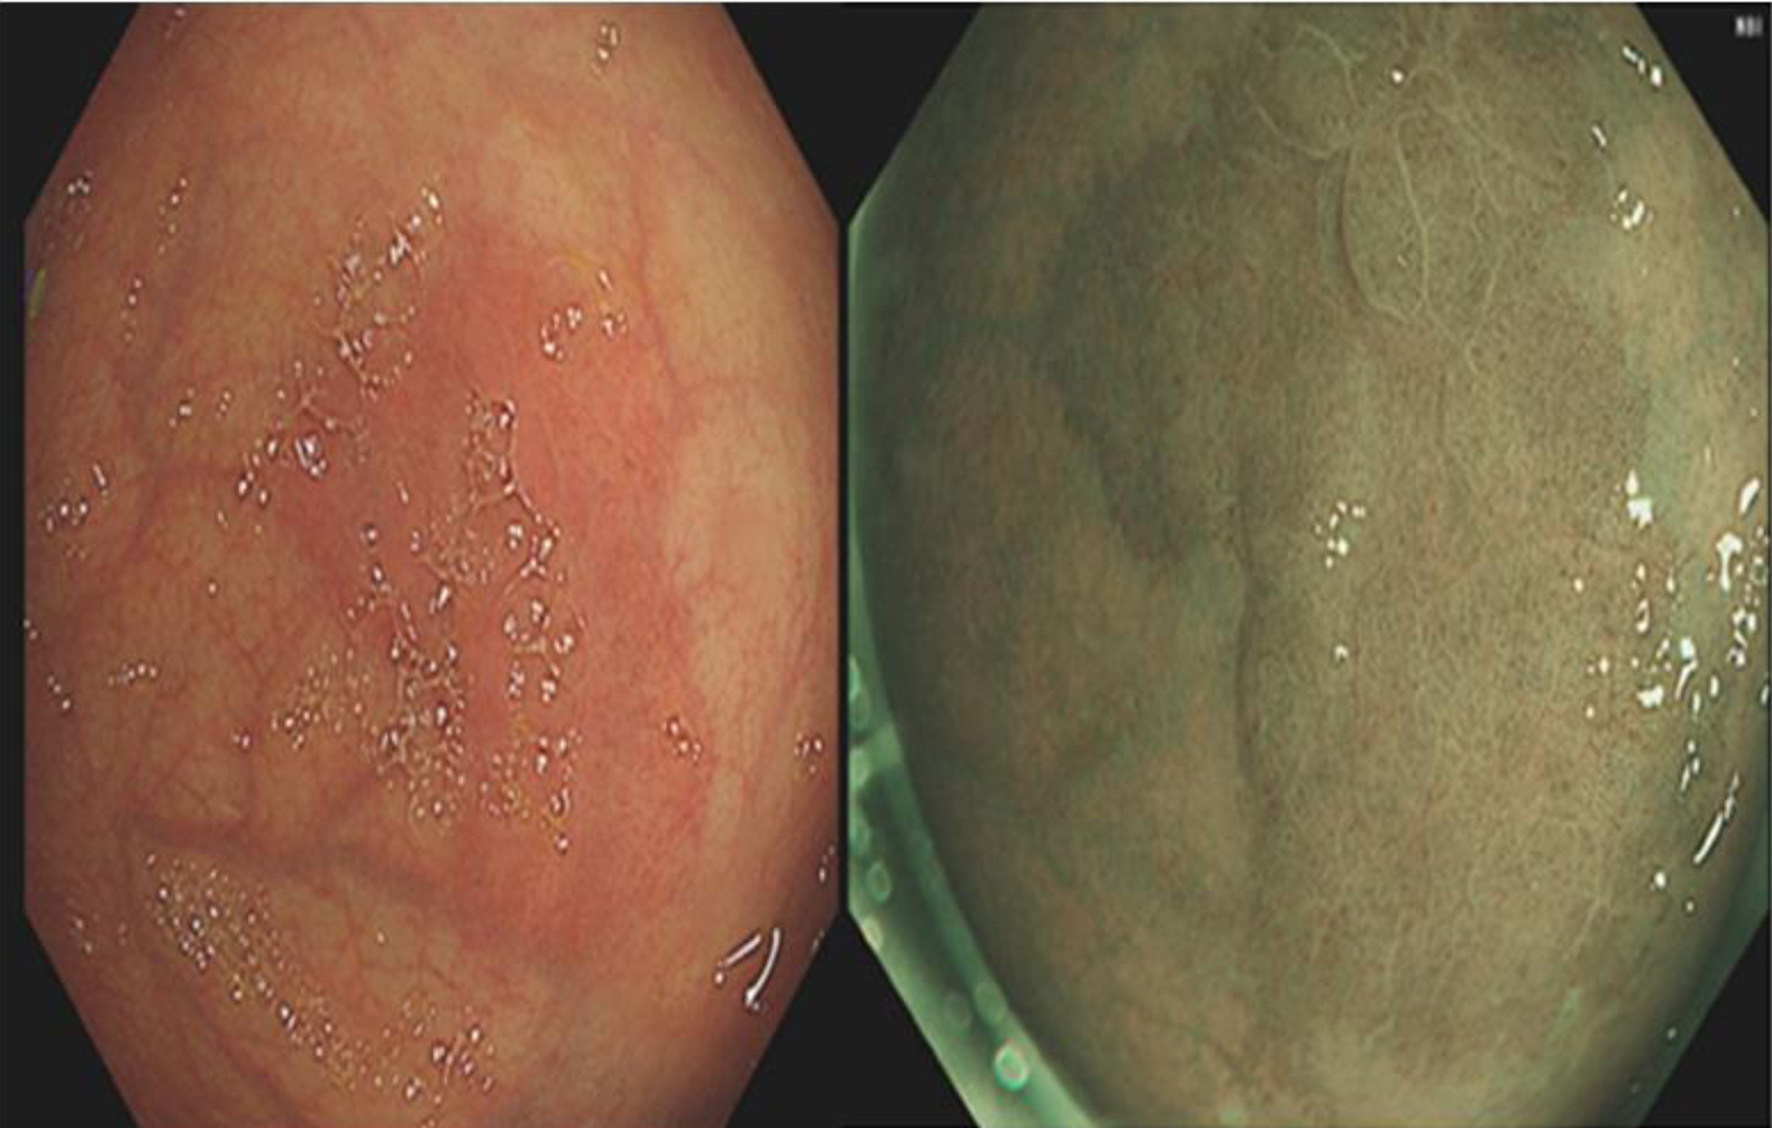

A 59-year-old Iranian male presented to his general practitioner (GP) with per-rectal bleeding and change in bowel habits. Blood investigation ordered by the GP showed no evidence of anemia but had a low white blood cell (WBC), red blood cell (RBC), and hematocrit. Table 1 displays the blood investigation results at the time of his initial presentation. He was subsequently referred via the 2-week wait pathway for colonoscopy. The colonoscopy revealed two polyps in the colon as well as a well circumscribed 15 mm erythematous patch in the rectum as shown in Figure 1. The polyps were removed, and the patch was biopsied at the time of colonoscopy. Pathology reported the polyps to be tubular adenomas with low grade dysplasia. The report also revealed the erythematous patch to consist of fragments of gastric fundic-type mucosa. Figure 1 displays the GHT found in the rectum. None of the biopsies showed evidence of dysplasia or malignancy. He also underwent an esophagogastroduodenoscopy (EGD) and computed tomography of the chest, abdomen, and pelvis (CT CAP) which were unremarkable as seen in Figure 2.

Figure 2. Computed tomography imaging did not reveal any abnormality. There was no evidence of malignancy.